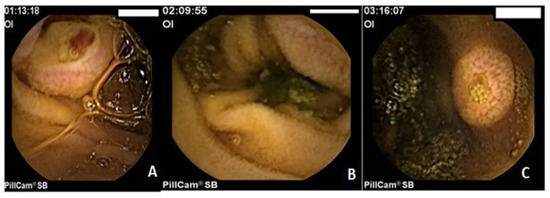

Metastatic melanoma is one of the most common malignancies associated with the spread of the primary tumor. The primary site is usually the skin or the eyes. The most frequent site of metastases is the gastrointestinal tract, accounting for 60% of cases at [...] Read more.

Metastatic melanoma is one of the most common malignancies associated with the spread of the primary tumor. The primary site is usually the skin or the eyes. The most frequent site of metastases is the gastrointestinal tract, accounting for 60% of cases at autopsy. In 2% of patients, metastases occur without a detectable primary tumor. We present a rare case of upper digestive bleeding caused by multiple gastrointestinal tract metastases from an amelanotic melanoma. This case report describes a 65-year-old male who arrived at the emergency department after experiencing an episode of upper gastrointestinal bleeding (melena). One week prior to admission, he had been treated with nonsteroidal anti-inflammatory drugs for lower back pain due to L4–L5 disc herniation. Upper digestive endoscopy revealed multiple polypoid masses in the stomach and duodenum, and capsule endoscopy showed additional lesions in the small bowel. Histopathological examination confirmed the diagnosis: metastases from an amelanotic malignant melanoma. Abdominal and cranial computed tomography scans revealed multiple secondary lesions in the brain, gallbladder, retroperitoneal area, gastrointestinal tract, and peritoneum. Localized radiotherapy was applied to the cerebral metastasis, and systemic chemotherapy with dacarbazine was initiated, resulting in a partial clinical response. Unfortunately, the disease progressed, and the patient died one month after diagnosis. Metastatic melanoma of the gastrointestinal tract is an exceedingly rare cause of upper digestive bleeding. Full article